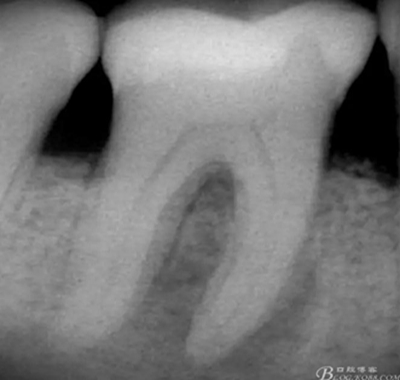

術(shù)前X片

高嵌體粘固后X片